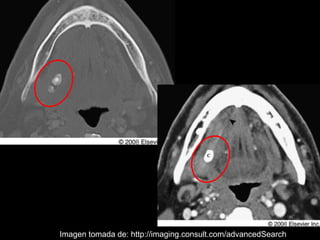

La sialolitiasis es la formación de obstrucciones mineralizadas en las glándulas salivales, causadas por el depósito de calcio y fósforo. Puede presentarse en las glándulas salivales mayores y menores, causando inflamación e hinchazón e incluso dolor durante las comidas. Los sialolitos se ven en radiografías como densidades radiopacas de varias formas y tamaños dentro de los conductos glandulares. El diagnóstico diferencial incluye otras imágenes radiopacas en los tejidos blandos.